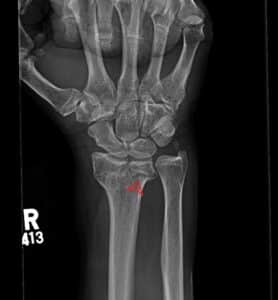

Die Punch – intraarticular impaction fracture of the lunate fossa.